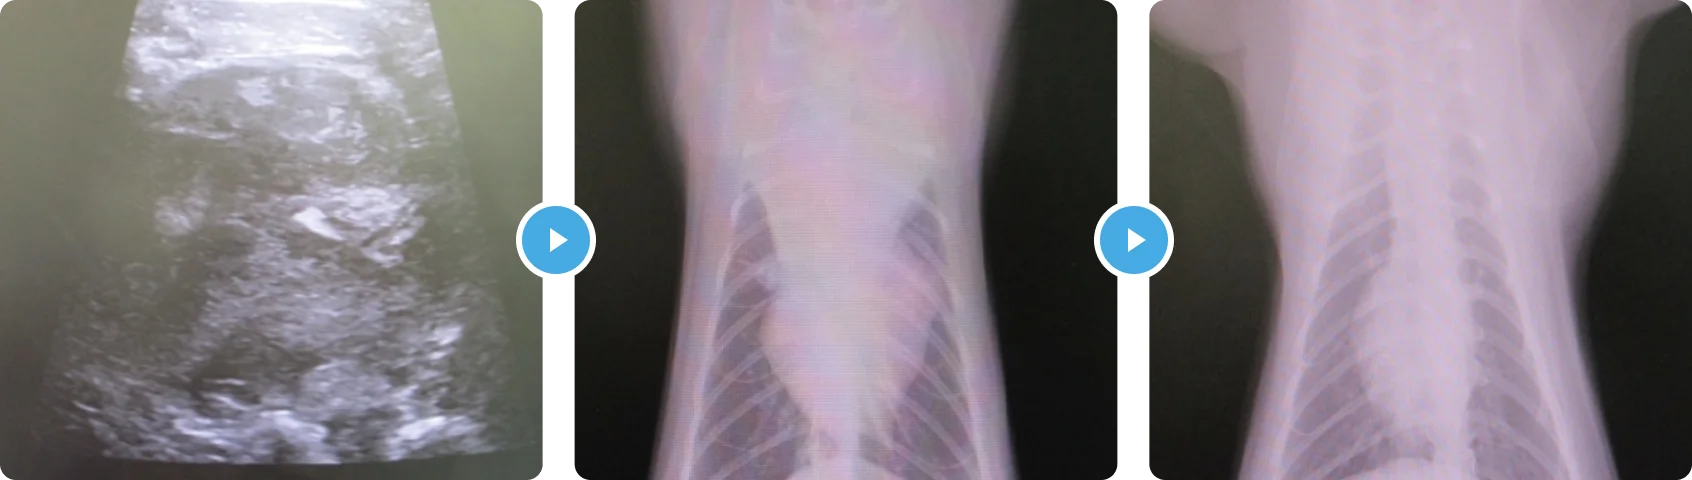

じゅうかくがたリンパしゅ 縦隔型リンパ腫

元気・食欲の低下を主訴にご来院いただきました。呼吸状態に問題ありませんでしたが、身体検査で心音の減弱がみられ、胸腔内病変が疑われました。胸部レントゲンでは、縦隔部に5cm大の腫瘤を認め、超音波検査では辺縁不整な低エコー腫瘤が観察されました。

また血液検査では臓器障害所見はありませんでしたが、白血病ウイルス陽性でした。後日鎮静下で腫瘤の細胞診検査を行い、大型リンパ球が多数採取され、病理検査では大細胞性リンパ腫との診断に至りました。

飼い主様とお話した結果、この子は投薬がかなり苦手であること、またお仕事の都合で通院に制限があること、ただ少しでも長く一緒にいたい、とのご要望をいただきました。そのため、Lアスパラギナーゼ、サイクロフォスファマイド、持続型ステロイドによるプロトコールによる治療を開始しました。

サイクロフォスファマイドは徐々に用量を上げていき、副作用等をみながら3週間ごとの投与にしていきました。約1年後に各種抗がん剤に耐性を示し、残念ながら亡くなってしまいましたが、ご家族と家で多くの時間を過ごすことができました。

白血病ウイルス陽性猫の縦隔型リンパ腫の中央生存は、2~3カ月とされています。多剤併用療法をおこなっても、早期に抗癌剤に耐性を示し、腫瘍の増大がみられます。最近の報告では、猫のサイクロフォスファマイドの最大耐久用量が以前より多いことが言われており、高用量投与での効果が報告されています。この子は比較的長期的に効果がでてくれ、副作用も最低限ですみ、長く頑張ってくれました。

はいがん(はいししょうこうぐん) 肺癌(肺指症候群)

片方の足を引きずって歩いているを主訴にご来院いただきました。

身体検査からは左前肢の爪に出血があり、爪の根元が腫れていました。その他、本人には症状がなく元気とのことでした。ただ爪をみると単なる外傷でなく見えたので、爪先の細胞診検査とレントゲンを撮りました。

その結果、爪の根元からはやや異型性のある上皮性系の細胞が採取され、肺には腫瘤がみられました。以上の所見より、「肺癌の爪先転移による跛行」と診断しました。

猫の肺癌は、時にサイレントキラーで症状なく進行していきます。

未分化な腫瘍細胞は血流にのり、指先でつまるのかそこに転移病変を作ることがあります。肺指症候群といわれ、予後の悪い肺癌といわれています。残念ながら、治すことは難しいため、痛みの緩和と苦しくなったら酸素吸入での対処をしていきました。